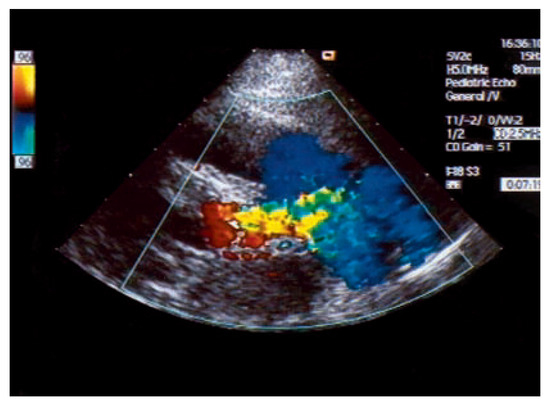

Asymptomatic Bland-White-Garland Syndrome in a 13-Year-Old Girl

by Jean-Pierre Pfammatter, Mladen Pavlovic and Stephan Windecker

An otherwise healthy 13-year-old girl was referred to the pediatric cardiology outpatient clinic for evaluation of a newly observed systolic murmur [...] Full article

Show Figures

Figure 1